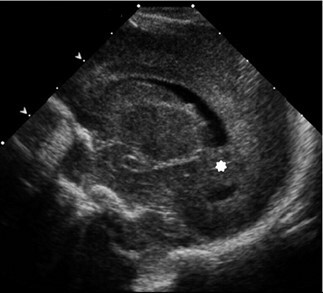

Neonatology Calcar Avis 2 Image